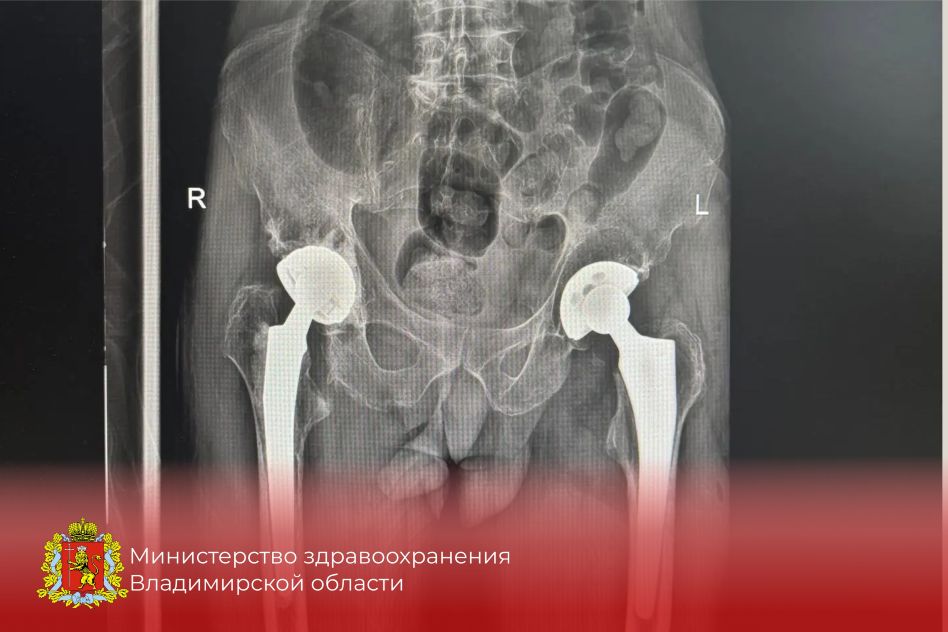

Оптимистичная информация пришла из областного министерства здравоохранения. Оказывается, за этот год в травматологическом отделении Центральной городской больницы Коврова хирурги установили более десяти эндопротезов тазобедренного сустава.

Сообщается, что это передовой метод лечения переломов тазобедренного сустава — той самой шейки бедра. И его ковровские врачи успешно освоили. Эта современная методика эндопротезирования позволяет, в частности, встать на ноги пожилым людям, которые сломали проксимальный отдел бедренной кости. А получить такой перелом человек за 60 может, даже упав с высоты собственного роста.

Фото: ВК-страница министерства здравоохранения Владимирской области.